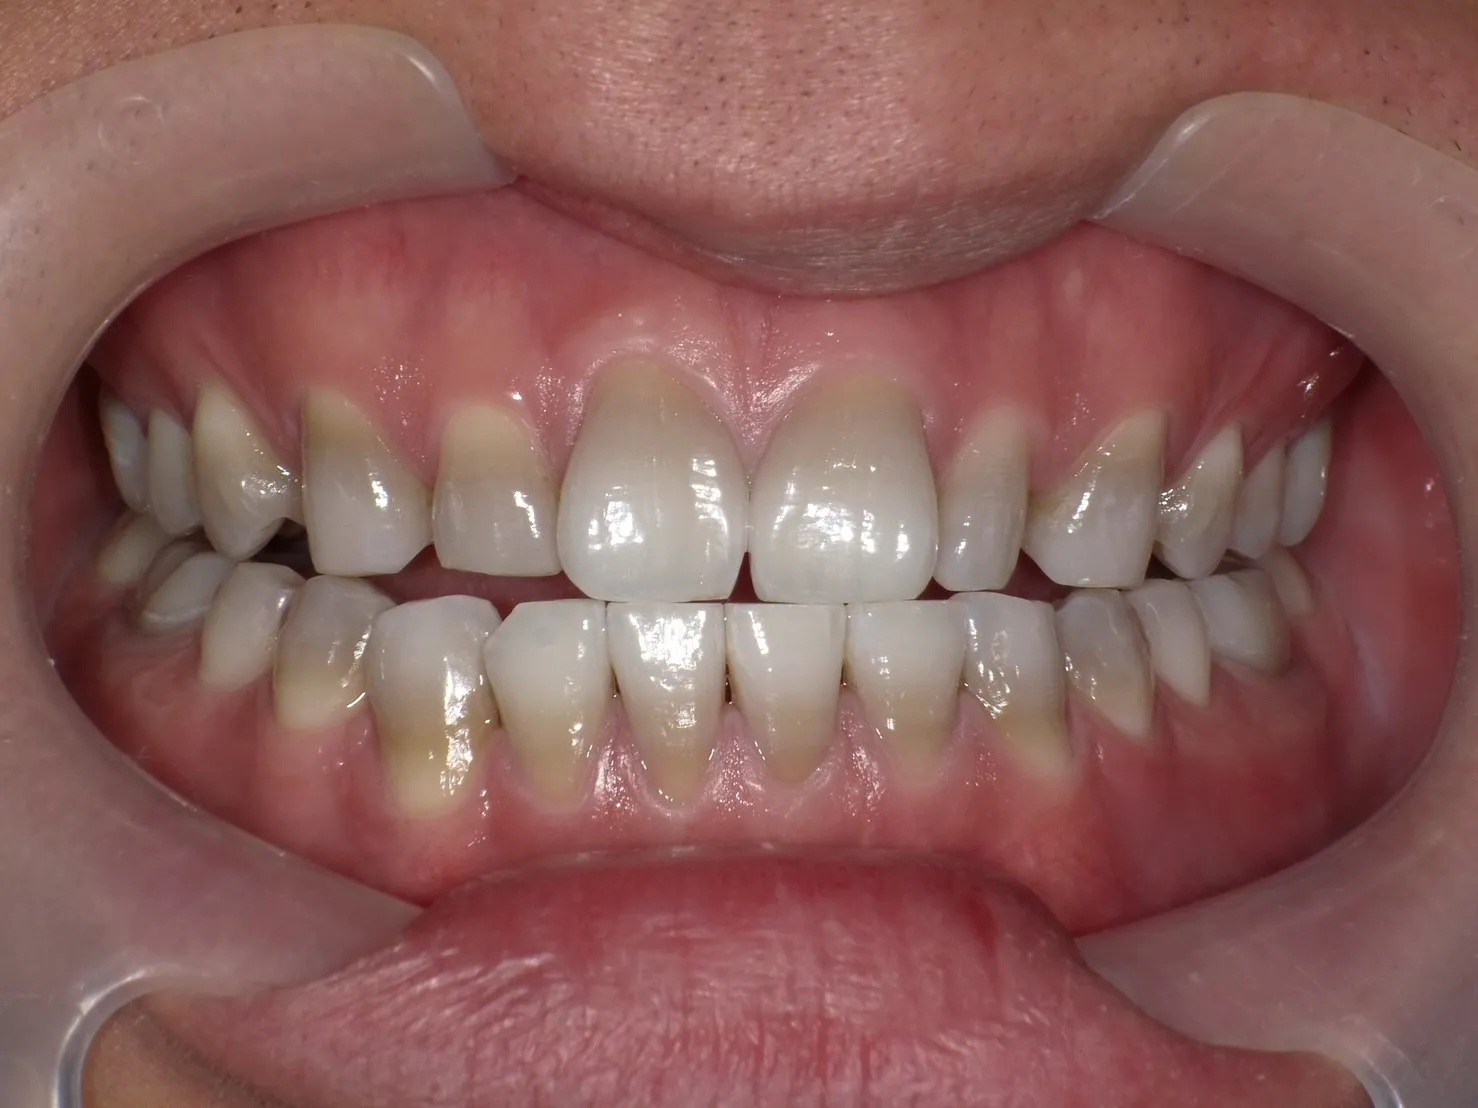

テトラサイクリン歯の治療法

テトラサイクリン歯の治療には、以下の方法が一般的に用いられます。

ホワイトニングは歯を削らないため、削らずに白くしてみたいという方に最適な治療法です。

特に、オフィスホワイトニングとホームホワイトニングを併用する

「デュアルホワイトニング」が効果的です。